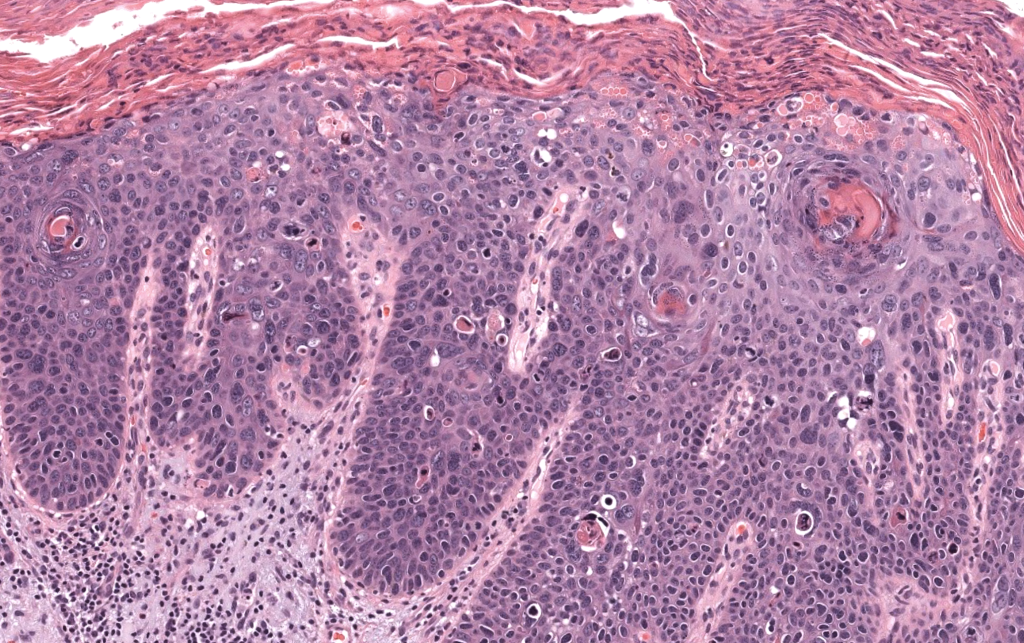

- Neoplasia maligna epitelial originada de queratinocitos epidérmicos, con distinta diferenciación escamosa, potencial de invasión local profunda y metástasis linfática/hematógena. Cassarino 2006, Motaparthi 2017

- Confirmación de CEC invasivo (no solo in situ).

- Grado de diferenciación (bien/moderado/pobre).

- Subtipo histológico (convencional, desmoplásico, fusocelular, verrucoso, etc.).